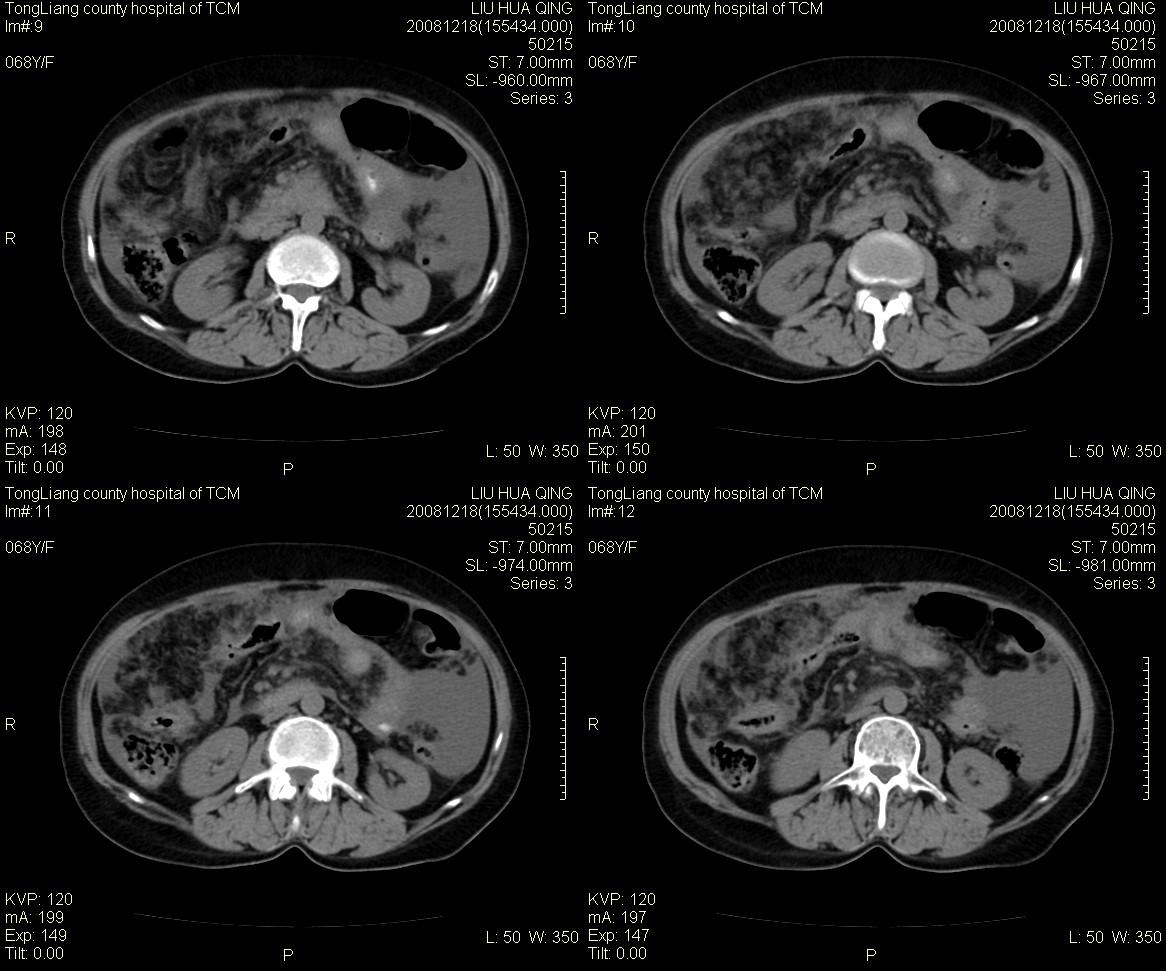

女,68y,下腹疼3月,一月半前院外ct示上腹未见异常。近1月来,症状加重。4天前入院,b超示胸腹水。今日呕吐频繁。  生化检查:  结核抗体阴性,血沉18mm/h, 癌胚抗原阴性,胸水细胞学检查见多数淋巴细胞。 白细胞总数5.4x10^12/l,血红蛋白104g/l.

患者右中腹部肠管聚集,内密度不均,可见片絮状及结节样增密影,小肠壁增厚,与之相邻处有软组织影。

腹腔积液可以肯定,原因?右侧下腹肠壁增厚,周围脂肪密度增高,粘连坏死?---梗阻坏死(不像)还是血栓坏死,占位?期待结果。

1)右侧腹腔前部见类似“网膜饼”样改变,考虑网膜转移瘤。2)腹水。

腹膜污染[大网膜增厚可见污垢征及小班结与饼片影,肠系膜增厚],大量腹水。考虑癌性腹膜炎,建议查腹水。结核待排.注意上腹部及胃肠道检查